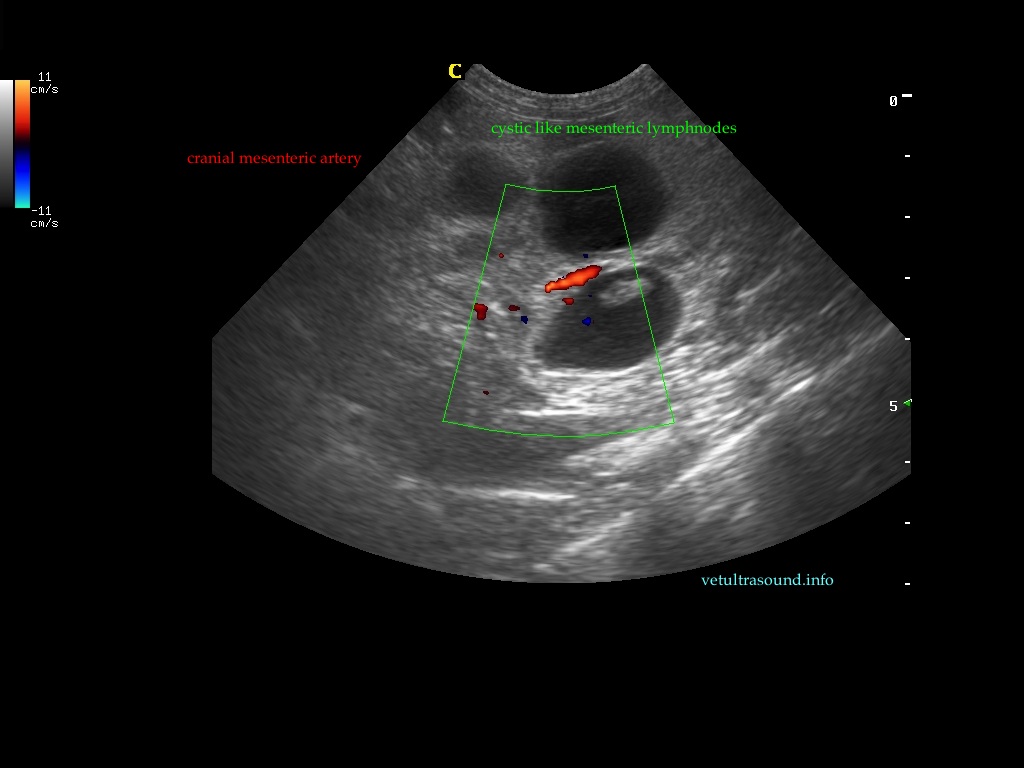

Findings: The ultrasound exam revealed a marked distention of a segment of the small intestine which ended in a narrowed lumen due to a thickened wall. The mesenteric lymph nodes were markendly enlarged and hypoechoic. A fine needle aspirate was performed.

After we decided the path of the needle, the insertion site was prepared with the Hibitane scrub and alcohol. Then we applied some gel on the Linear probe and covered with the elastic glove. Then the syringe was loaded with 5ml of air and attached to the needle. We performed techniques with and without aspiration depending on the blood that sometimes was withdrawn. The diagnosis was Lymphoma.

The GIF shows the frames from the normal small intestinal layering to the thickened abnormal wall in a perpendicular view.